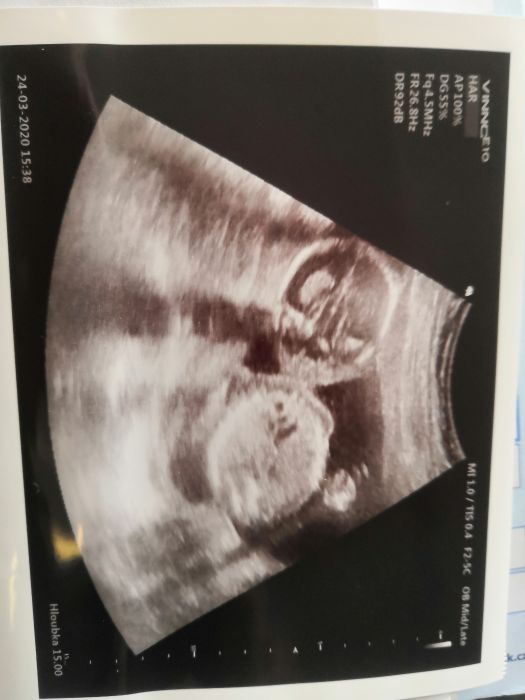

Tak kontrola proběhla včera a byl to hrozný frmol.. Ani jsem si to neužila.. Snad to bude příště lepší.. Prevenci doktor zrušil a dělá jen akutní případy a tehulky.. A pohlaví zase nic.. Asi se stydí ten náš šmudlik

Posílám fotku

[1138343] pardon nejak se mi to odeslalo driv, moc pekne foto, uz se taky tesim?